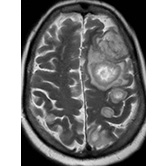

Neuroradiology — Cerebral Aspergillosis Jacob Wallace, MD |

![]() |